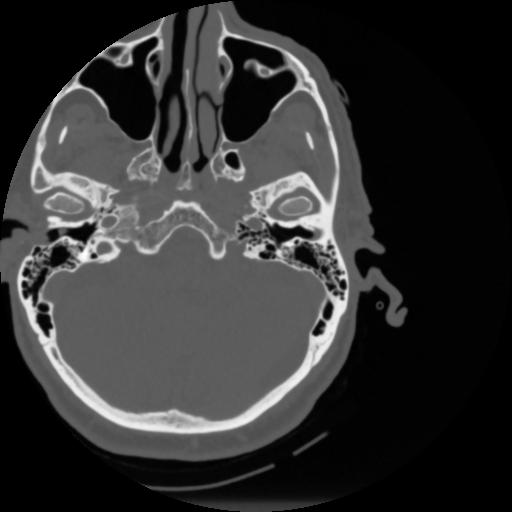

4 CEREBRO,,Vol,0.5,CEREBRO,,